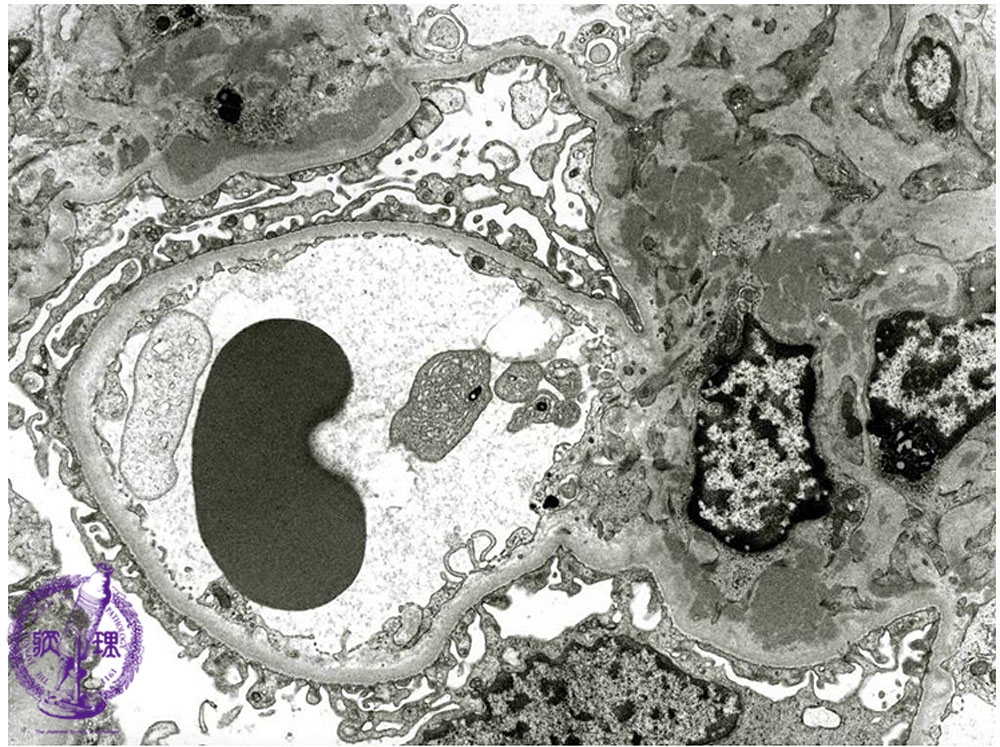

- ★(4)IgA nephropathy

Microscopic findings (electron microscopy): In the mesangium (yellow dotted line), there is are electron dense deposits (red dotted line). The basement membrane is not thickened (red arrows).